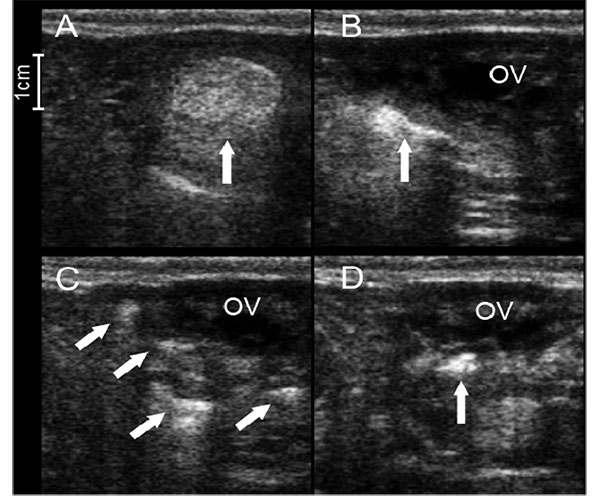

Evaluation of tubal patency with hysterosalpingo-contrast sonography using sodium alginate solution and the subsequent fertility outcomes in repeat breeder cattleKazuki ITO, Ryuji HASHIMOTO, Natsumi ENDO, Tomomi TANAKA

J Reprod Dev. 2025 Nov 2;71(6):310–314. doi: 10.1262/jrd.2025-052